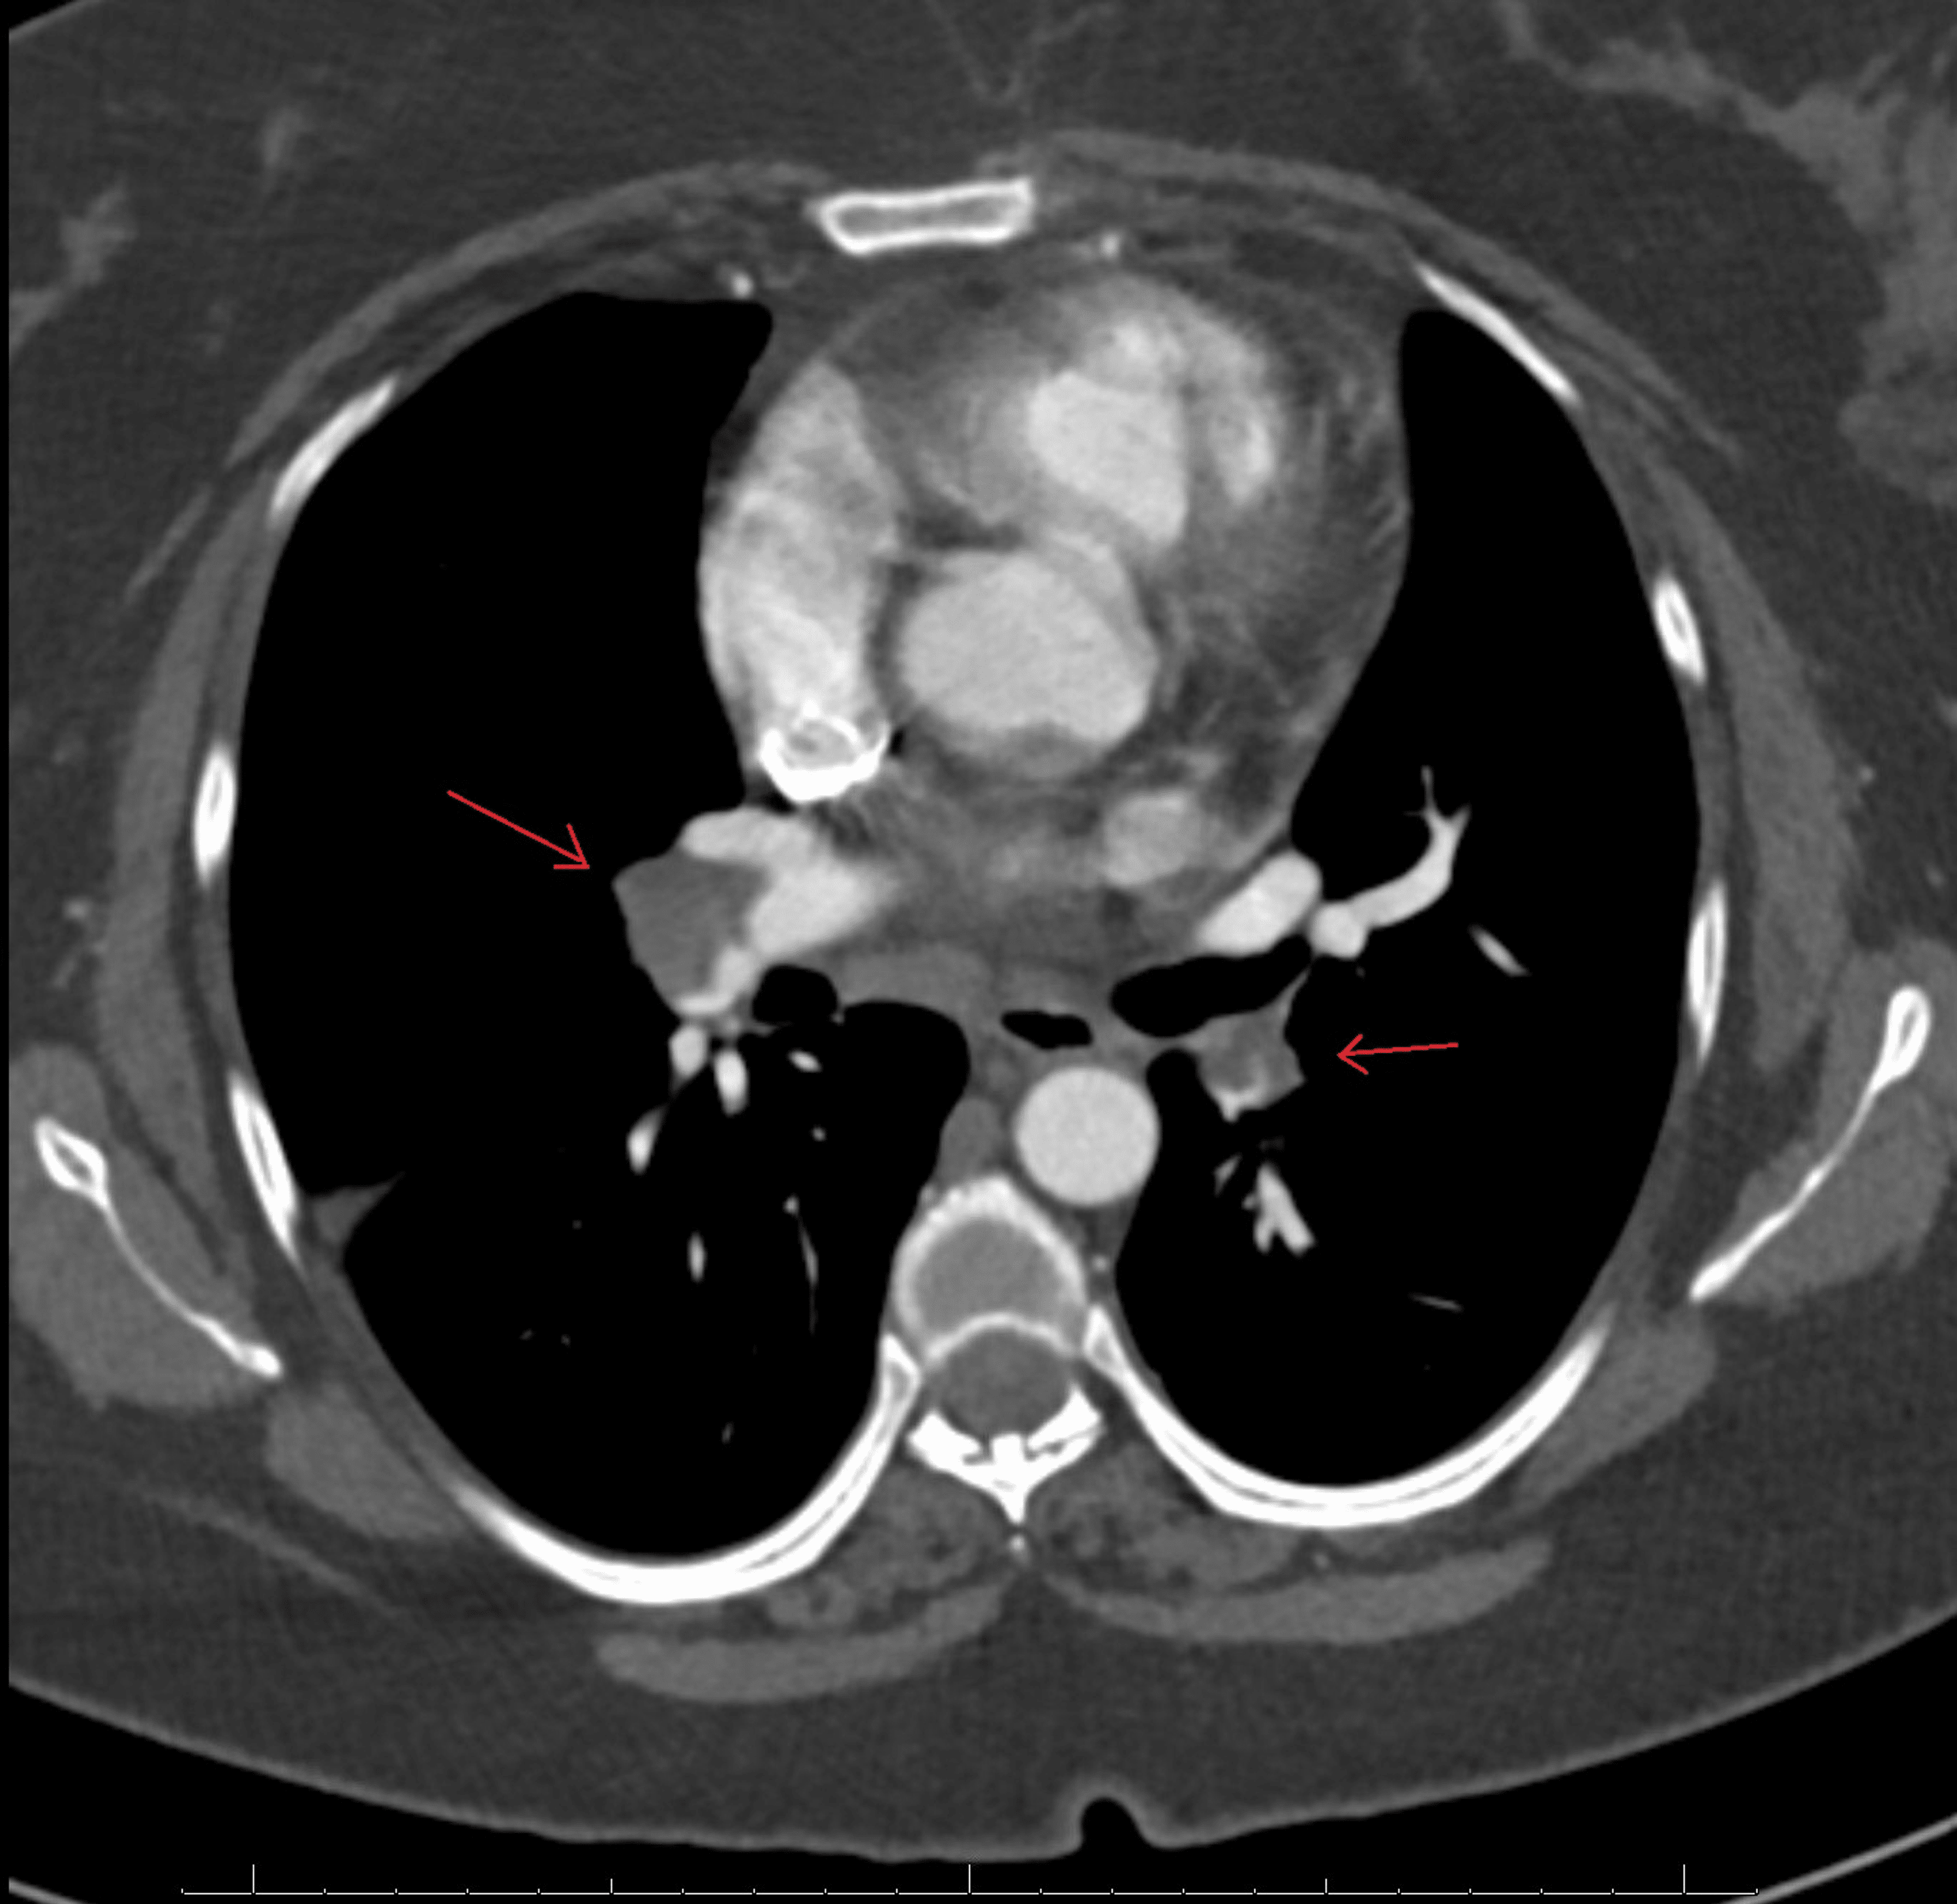

From www.researchgate.net

(PDF) Hereditary protein S deficiency presenting acute pulmonary embolism Protein S Deficiency Pulmonary Embolism Conditions such as protein s deficiency, resulting from genetic mutations, are encompassed within this category of causative. Protein s deficiency is an inherited thrombophilia associated with an increased risk of thromboembolism. Subjects were regarded protein s deficient when protein s levels were <2.5th percentile of the controls. Having this deficiency puts you at risk for a blood clot in your. Protein S Deficiency Pulmonary Embolism.